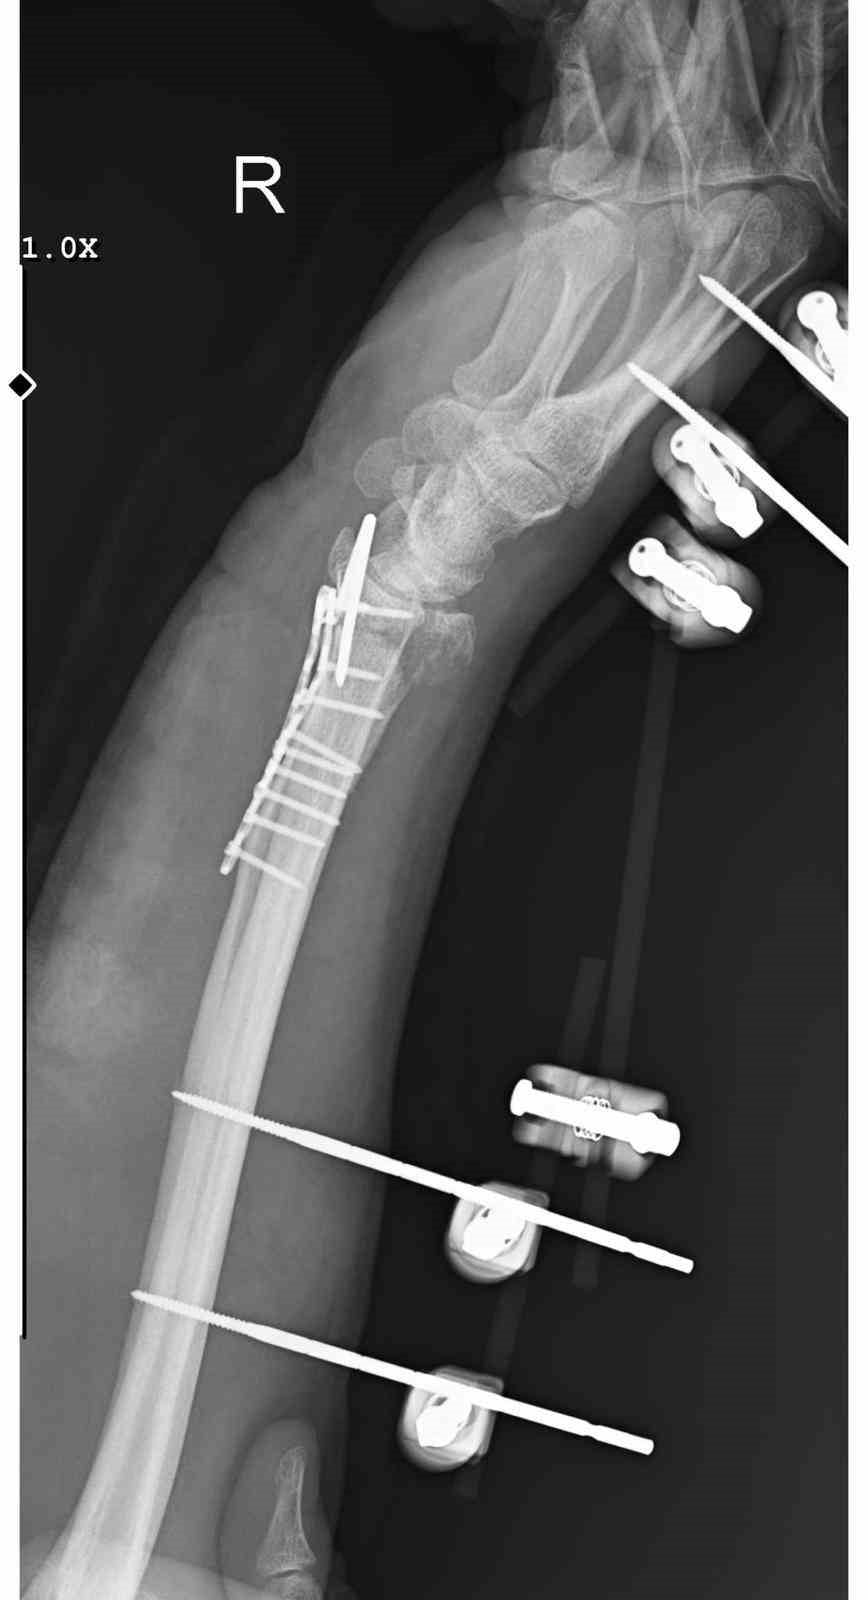

29 Aralık günü Mamak'ta meydana gelen olayda, 35 yaşındaki Yasin Arslantaş yaşadığı apartman önünde sahipsiz köpekler tarafından kovalandı. Kaçmaya çalışırken düşen Arslantaş'ın el bileği kırıldı; ameliyatla bilek kemiğine 11 adet platin takıldı ve kolunda kalıcı his ile hareket kaybı riski oluştu.

Alınan bilgilere göre, Arslantaş apartmandan çıkış yaptığı sırada yaklaşık 10 sahipsiz köpek tarafından kovalandı. Kaçmaya çalışırken ayağının kayması sonucu düştü ve el bileği kırıldı. Hastaneye kaldırılan Arslantaş ameliyat edildi ve bileğine 11 platin yerleştirildi. Olay sonrası maddi ve manevi zarara uğradığını söyleyen Arslantaş, belediye ekiplerinin başıboş köpeklerle yeterince ilgilenmediğini iddia etti.

Arslantaş olayla ilgili, "Sabah apartmandan çıkış yaptığım sırada arkamdan 9 köpeğin geldiğini gördüm. Saldırgan haldelerdi. Bana saldırmak üzerelerdi. Kaçmaya çalışırken ayağım kaydı ve düştüm. Bileğimde 15 dikiş ve 11 platin var. İki ay boyunca kolum bu halde kalacak ve ardından da yine 2 buçuk ay fizik tedavi süreci olacak. Doktorlar his ve hareket kaybımın olacağını söylediler. Bileğimden büyük kemiğin kırılmasından dolayı zorlu bir süreç geçiriyorum. 3 saatlik bir ameliyat geçirdim" dedi.